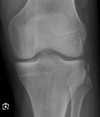

14 yo M with knee injury while playing football ~ hyperextension and direct trauma. Unable to WB Diagnosis?

Tibial spine fracture (intercondylar eminence) **associated with ACL rupture More common in children MOI- twisting knee movement, hyperflexion, hyperextension Immediate pain and swelling after injury XR: There is an avulsion fracture (red and white arrows) of the intercondylar eminence. There is a also a large suprapatellar hemarthrosis (yellow arrow). Such fractures are associated with injury to the anterior cruciate ligament.